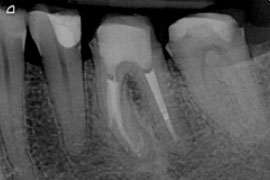

Revisionsbehandlung

Wurzelkanalbehandelte Zähne können grundsätzlich genauso lange wie nicht wurzelkanalbehandelte Zähne erhalten bleiben – im Idealfall also ein Leben lang. Da jedoch die Wurzelkanalbehandlung eine der kompliziertesten zahnmedizinischen Eingriffe darstellt, ist es möglich, dass eine Wurzelkanalbehandlung in einigen Fällen nicht den gewünschten Erfolg erzielt.

Um den betroffenen Zahn dennoch zu erhalten besteht die Möglichkeit eine erneute Wurzelkanalbehandlung, eine sogenannte Revisionsbehandlung, durchzuführen. Dies kann notwendig sein, wenn:

Der Zahn wird mittels eines Spanngummis isoliert, die Hohlräume werden aufgesucht und das vorhandene infizierte Füllmaterial wird entfernt. Dann erfolgt die erneute Reinigung, die bei einer Revisionsbehandlung oftmals schwieriger und zeitaufwändiger ist. Unter Berücksichtigung des Einzelfalles wird in das gereinigte Wurzelkanalsystem bis zum folgenden Termin vielleicht ein Medikament eingebracht. Zur Behandlung kann es nötig sein eine vorhandene Krone oder Brücke zu entfernen, um das Wurzelkanalsystem zu erreichen.

wurzelgefüllter Zahn mit Entzündung an der Wurzelspitze; zusätzlich ist eine abgebrochene Feile zu sehen

1. Entfernung von 2 Fragmenten aus mb1

2. Revision und Perforationsdeckung bei via falsa